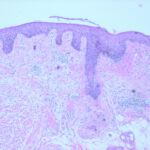

Histopathology. The earliest change consists of acantholysis in the upper epidermis, within or adjacent to the granular layer, leading to a subcorneal bulla in some instances . More commonly, enlargement of the cleft leads to detachment |

of the stratum corneum without bulla being seen. The number of acantholytic keratinocytes is usually small, often requiring a careful search to identify them. Secondary clefts may develop, leading to detachment of the epidermis in its mid level. These clefts may extend to above the basal layer, rarely giving rise to limited areas of suprabasal separation. In the setting of a subcomeal blister, dyskeratotic granular keratinocytes are diagnostic for this disorder. Eosinophilic spongiosis may be prominent with intraepidermal eosinophilic pustules. Thus, the histologic features of pemphigus foliaceus may have three pattems: {a} eosinophilic spongiosis; {b} a subcorneal blister, often with few acantholytic keratinocytes; and {c} a subcorneal blister with dyskeratotic granular keratinocytes , diagnostic of this disorder. The character of the inflammatory infiltrate is variable and depends on the age of the lesion, whether a blister is present, whether the superficial portion of the epidermis has been detached, and whether there is impetiginization or necrosis of the blister roof. |